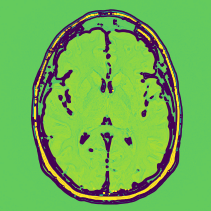

(d) Benign SD

Figure 11: Proposed preprocessing applied over benign MRI images.

Figure 11 shows a transition of the various stages of the proposed preprocessing for a benign brain neoplasm. The contour of the benign brain produces many yellow regions as shown in Fig. 11(b). But when compared with the difference contour, the less interesting regions are colored green with a brown border. Further, a brown edge with yellow is is seen in the final image where the benign neoplasm is present as seen in Fig. 11(d). This means the proposed preprocessing can intensify the regions with benign neoplasm than the other regions.